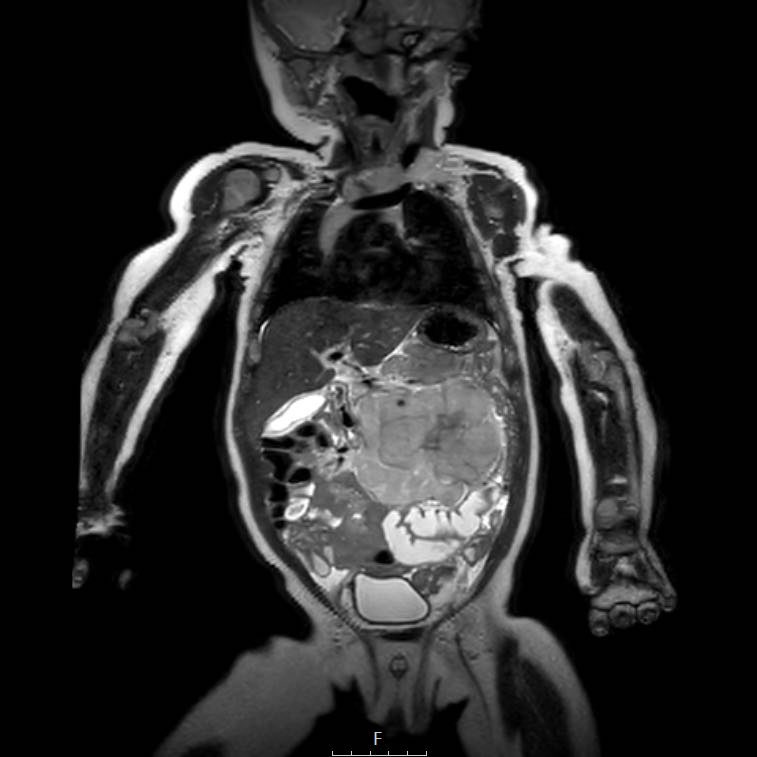

Cuộn qua chuỗi ảnh T2 theo mặt phẳng coronal.

Nghiên cứu các hình ảnh và sau đó tiếp tục đọc.

The findings are:

- Mass with encasement of the aorta and splanchnic vessels.

- Lan rộng dọc theo cột sống ngực nhưng không xâm lấn vào ống sống.

- Small liver metastases.

- Left supraclavicular mass.